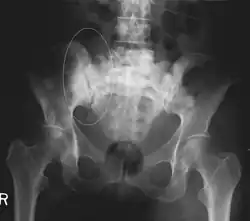

Skeletal radiography

A plain film x-ray of the entire body can identify bone metastasis. However, the sclerotic or osteolytic lesions must be at least 1 cm in diameter.[15] A combination of X-ray, CT and MRI scans may be most sensitive in the diagnosis of cancerous bone metastasis.[15]